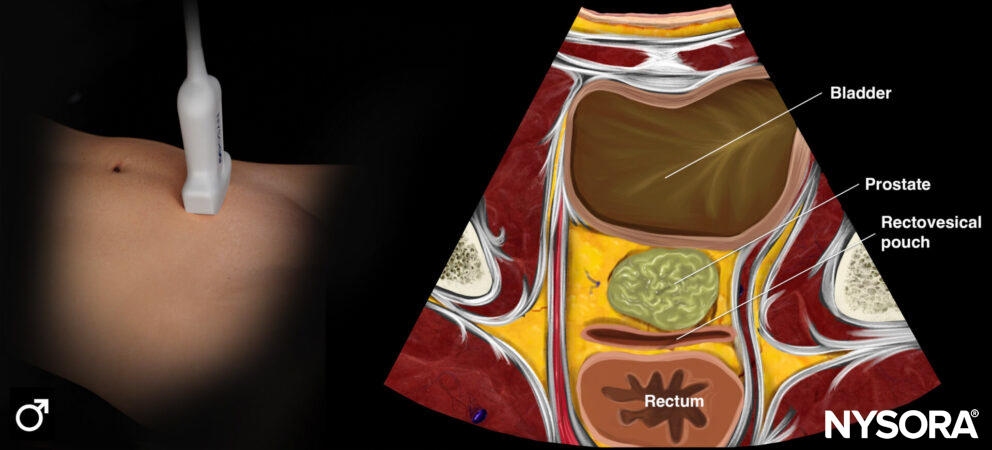

Transverse ultrasound view of the bladder (male).

Longitudinal Reverse Ultrasound Anatomy of the bladder (male).

- There is no difference in bladder anatomy for a male or female, except for the underlying anatomy.